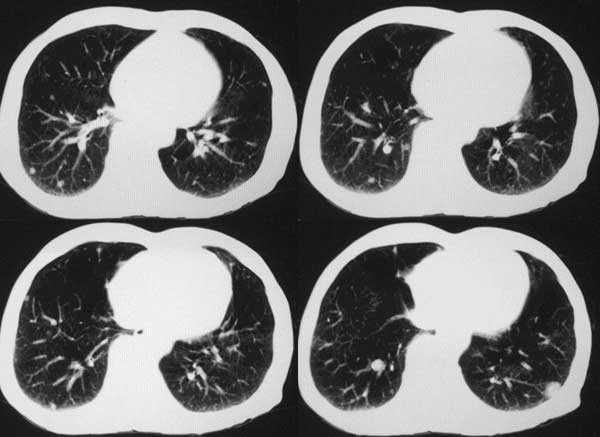

患者,男79岁,左侧肾癌术后5个月。近三个月,咳嗽时有痰中带血。

本例病人肺内多发结节灶、双侧肋骨破坏、胸椎椎体及椎弓破坏应是肾癌转移。请大家分析气管内结节灶性质?另外还得麻烦领导给删掉那多余的那幅图。谢谢了!

双肺多发结节状影,腹膜后见肿大淋巴结,支持肾ca转移

支持肺内 肋骨 椎体转移。

双肺内多发结节影是转移灶没问题,气管内的还应该商榷

肺内 肋骨 椎体转移已确定,气管内阴影不象结节,气管内壁无增生,显示层面只有一层,纵隔窗见不到,多考虑粘痰核.